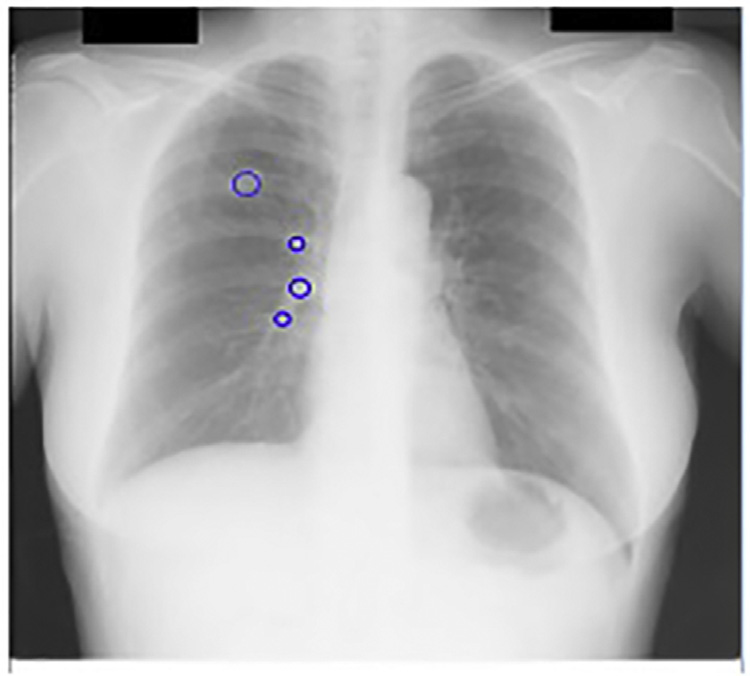

使用主成分分析滤波器进行肋骨抑制的结果如图14.2B所示。采用标准的高斯检测器高斯拉普拉斯掩模(LOG)来寻找可能存在结节的峰值区域。在原始胸部X光图像中应用该掩模导致了大量的假阳性,如图14.2A 所示,其中许多假阳性出现在肋骨上。

然而,在使用主成分分析滤波操作进行肋骨抑制后,该掩模除了检测到真正的结节外,仅产生了极少量的假阳性。人们认为,假阳性数量的减少主要归功于对肋骨的有效抑制。

采用PCA滤波作为预处理步骤的CAD方案输出(图14.19)。PCA滤波抑制了肋骨,从而消除了发生在肋骨上的假阳性。PCA滤波还增强了被肋骨遮挡的结节。

我们的最终第四种策略是将主成分分析滤波后的肋骨抑制图像作为计算机辅助诊断系统的输入。图14.20中可明显看到肋骨抑制的效果。采用主成分分析滤波后,每幅图像保留的候选结节平均数量降至三个。在肋骨边缘会检测到大量假阳性,而当输入为肋骨抑制图像时,这些假阳性被有效去除。此外,主成分分析滤波还提高了计算机辅助诊断系统的敏感性,因为被肋骨遮挡的癌结节变得更加显著。